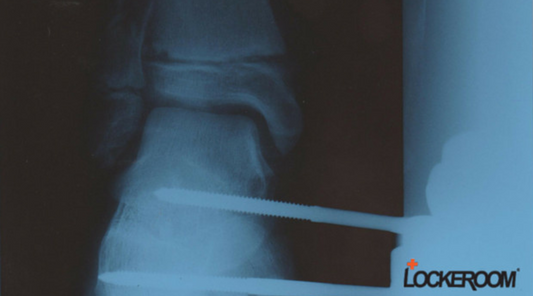

- Fractures: The wrist is prone to fractures, particularly of the scaphoid bone, often resulting from a fall on an outstretched arm or a direct impact, such as punching. Symptoms typically include localised pain, swelling, and tenderness. Treatment usually involves immobilisation with a brace or plaster cast, and in some cases, surgical intervention may be necessary.

- Scapho-Lunate Injuries: These injuries often result from falls on an outstretched arm and can lead to pain, swelling, and reduced wrist function. Treatment may involve bracing, physical therapy, or surgical intervention if the injury is severe.